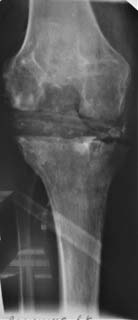

Уважаемые коллеги! Пациент мужчина 62 года эндопротезирование коленного сустава в

сентябре 2011 в одном из соседних учреждений. Множественные операции по восстановлению

связок в анамнезе

Под наше наблюдение попал спустя 3 месяца с клиникой глубокой перипротоезной инфекции.

Гнойный свищ, MRSA в посеве. Выполнено удаление протеза, некрэктомия, установка

цементного спейсера. Заживление первичное, а\б терапия по посевам, в течении 2 месяцев

положительная динамика, нормализация лабораторных показателей. В последующем усиление

болей, отек, разрушение спейсера по рентегнограммам. Взят в операционную для повторной

некрэктомии, удаления спейсера. Во время операции выявлено- отсутствие явного гнойного

содержимого, ткани более жизнеспособные чем во время первого удаления, отсутствие

значительного прогрессирования костных дефектов. Решено от одномоментного артродеза

воздержаться, конечность стабилтзирована дистракционным аппаратом. В

интраоперациооных посевах St.aureus В настоящее время две недели после операции, встает

вопрос о возможностях далнейшего лечения. Ревизонное колено? Еще раз после спейсера или

сразу? Или артродез